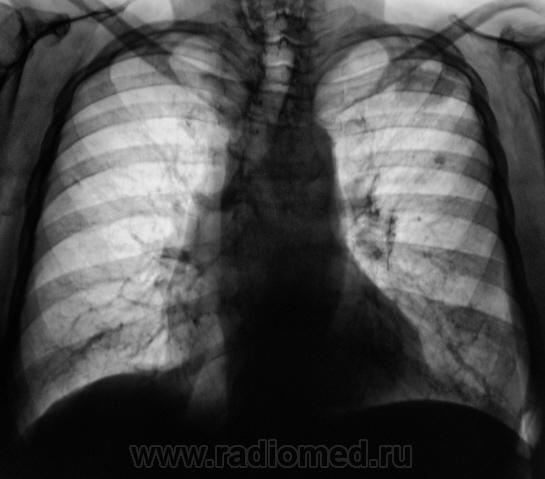

А, на верхушке, тихо "улыбалась" фокусная тень.

Жалоб нет. Ваше мнение уважаемые коллеги?

Прослеживается связь с корнем, плевра утолщена, рядом очаговая тень(отсев?), скоре всего туеркулез.

А, если туберкулёз, то, по всей видимости, инфильтративный?

Да, возможно даже каверна сформируется, фокус достаточно крупный, неоднородной структуры.

учитывая отсутствие клиники, наличие неоднородной фокусной тени, отсев? на первый  план в диф. ряд можно выставить туберкулез, сделать Т-грамму левой верхушки, и пусть терапевты проведут минимальные обследования...

Слева в S2 похоже на туберкулому (очерченные контуры в отличии от инфильтрата).

Коллеги!!! Спокойный окружающий фон, отсутствие четкого контура, мелкая лучистость по периферии образования, лимфангит к корню, подходящая интенсивность. По-моему здесь классический периферический рак.

Во- первых:я бы сказал, что окружающий фон не совсем спокойный, т.к. за III ребром очаг.Во-вторых периферический рак лёгого (бронха), как правило растёт вдоль длинника бронха- мы этого в данном случае, не видим. В-третьих: при туберкулёзе, то же бывает "дорожка" к корню. Так, что говорить о классическом периферическом раке легкого не стоит.

Есть все основания для подозрений в сторону периферического рака...  Кроме того насторожила картина в нижней части правого корня - нет полоски Прозорова.

Выскажу свою точку зрения в "защиту" рака. 1. Одиночный кальцинат за III ребром - это, во-первых, не тот окружающий фон в широком смысле этого слова. А во-вторых, сочетание TBC и c-r очень частое явление (хотя раньше считалось казуистикой). 2. В экспансивную стадию роста c-r растет в сторону наименьшего тканевого сопротивления. Для субплевральной локализации в в/д характерна "приплюснутость", когда длинник фокуса расположен параллельно грудной стенке из-за увеличения давления на наружный и внутренний края образования при дыхании. 3. При TBC "дорожка" к корню чаще бывает нечеткой, смазанной вследствие паравазальной инфильтрации (процесс-то инфекционный). При раке - "чистый" лимфангит. Кроме того - неоднородность структуры (многоузловой рост, возможно и распад).

Итак, если, я правильно понял, то дифференциальную диагностику нужно проводить между периферическим раком легкого и туберкуломой?